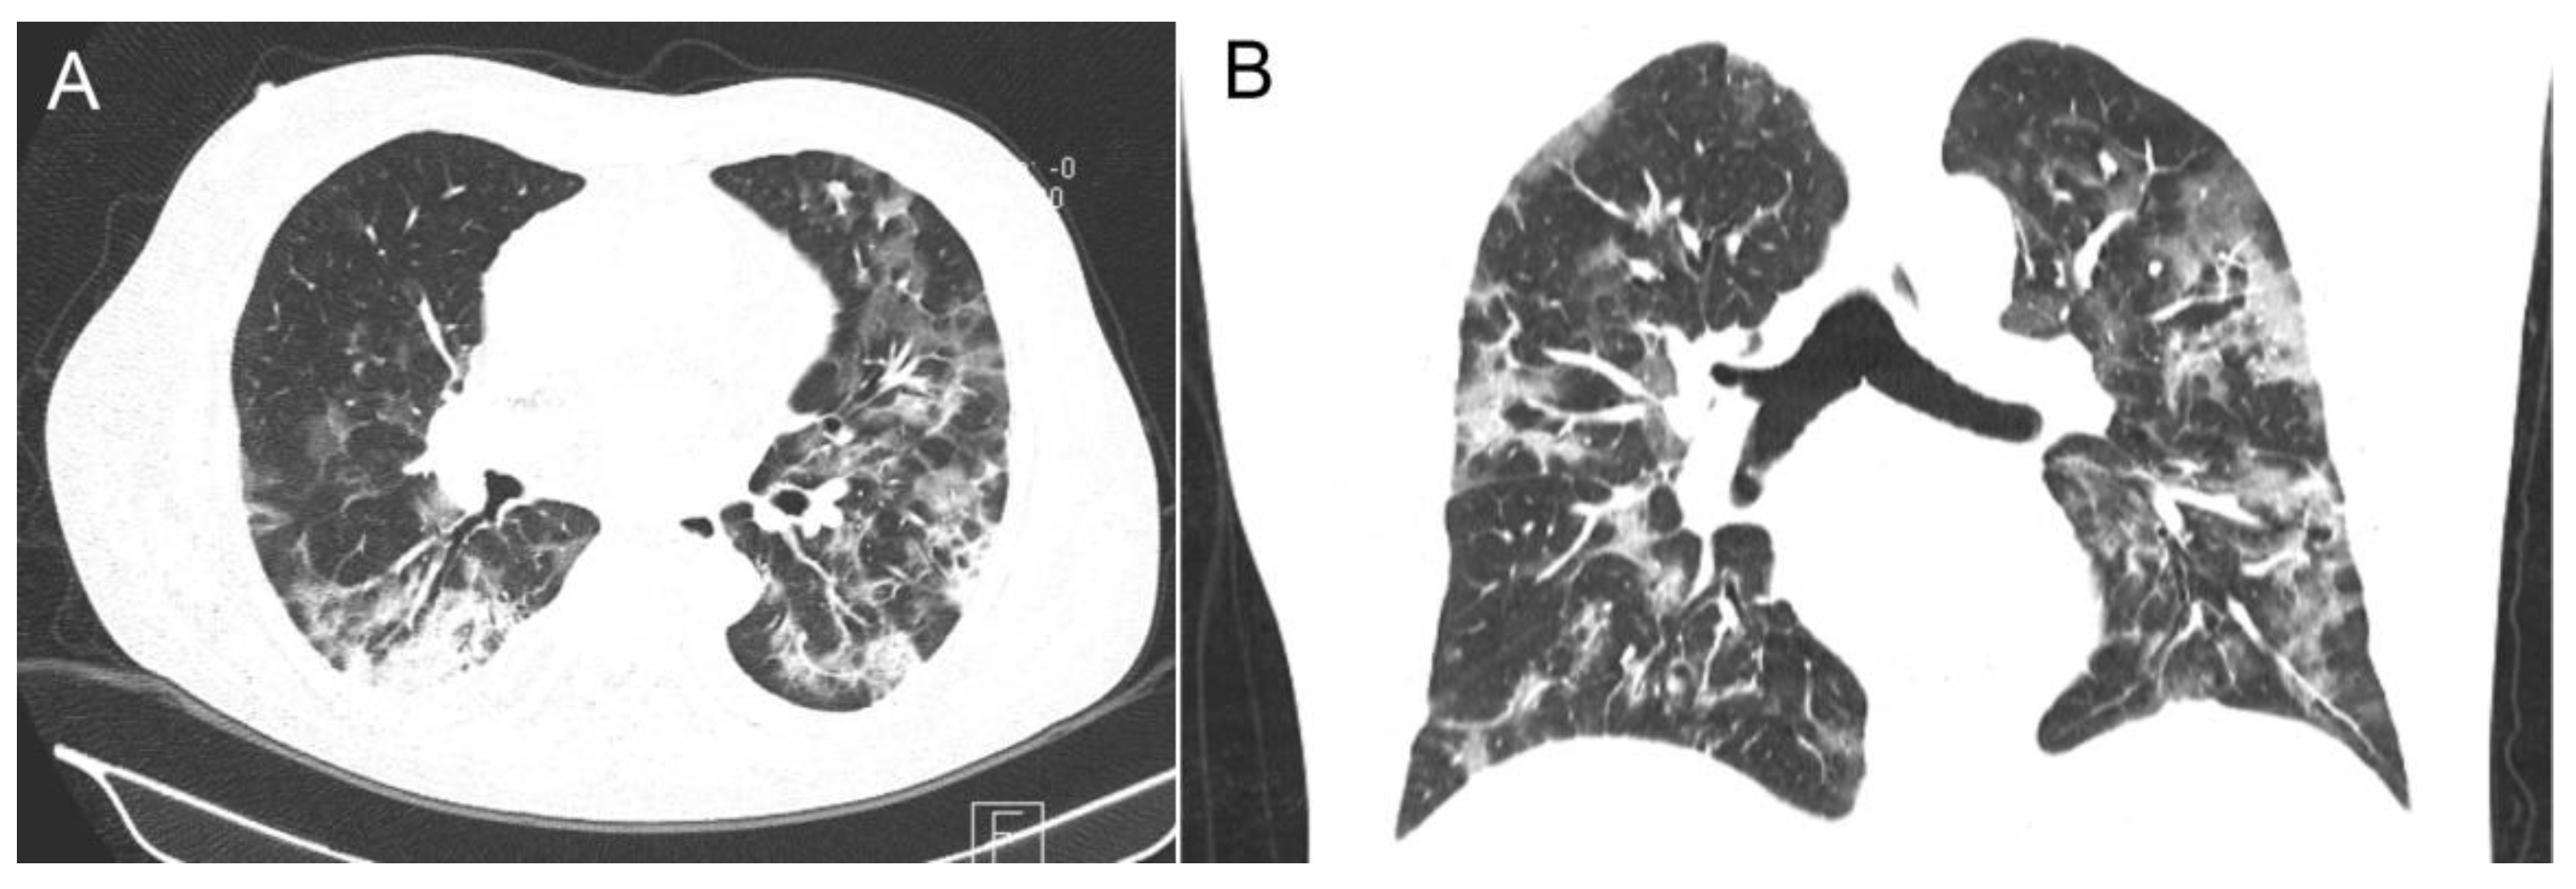

| Radiological findings | |

| X-ray, bilateral pneumonia, n (%) | 131 (95.6) |

| CT-score; n (%); median; range | 66 (48.2); 18.2 (8–25) |